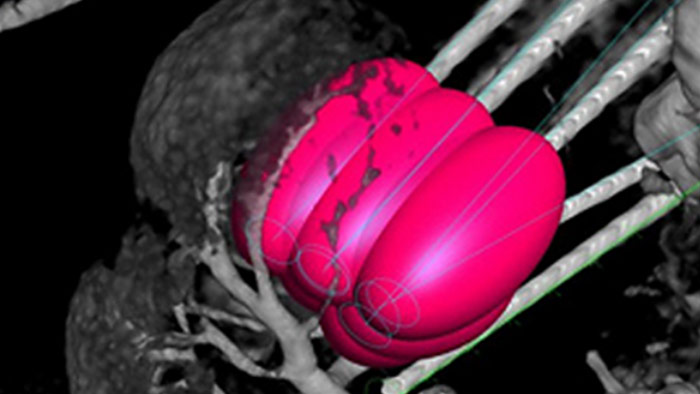

XperGuide Ablation* provides comprehensive assistance for treatment planning and live needle guidance. It offers unique Parallax Correction to plan needle trajectories for off-center lesions.1 To optimise the needle position for effective ablation, this tool displays the virtual needle path to assist in multiple needle planning. It shows needle characteristics such as ablation zone/isotherm to confirm complete tumor coverage prior to ablation.

Percutaneous ablation (radiofrequency, microwave, and cryoablation), is a well-established minimally invasive treatment of kidney, liver, lung and bone tumors. It is critical to define the tumor boundaries and decide on an optimal number of needles and corresponding needle trajectory to be able to perform a complete tumor treatment and not to cause damage to surrounding tissue. Navigating accurately at low dose to the lesion of interest without needle repositioning increases the opportunity for success and reduces risk for complications of your biopsies or ablations. Confirmation of ablation treatment endpoint can be accomplished with 3D imaging while the patient is still on the table.